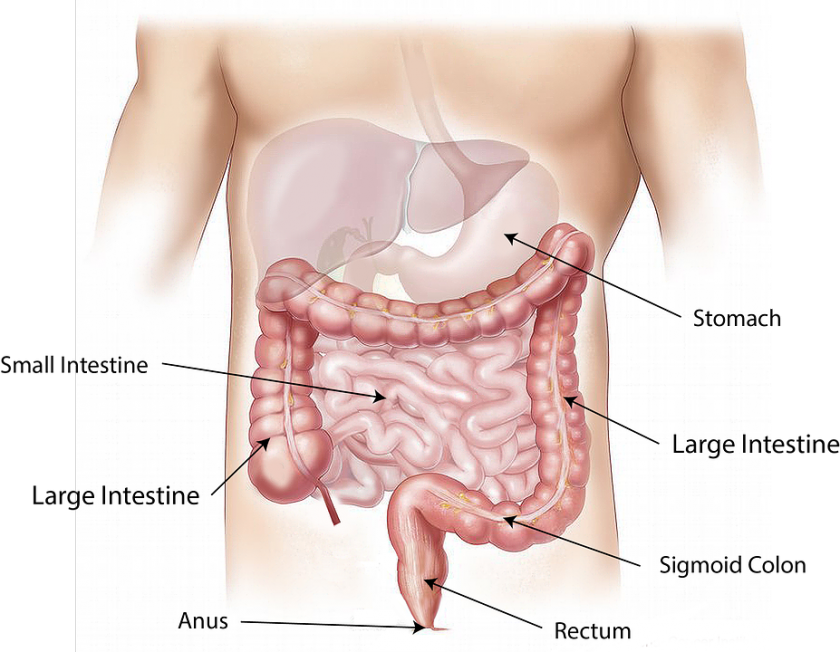

Ulje štapića cimeta moćno deluje na jačanje cirkulacije krvi, pa tu leže i mnoge druge beneficije koje cimet poseduje. Daje osećaj topline i opuštenosti. Čisti krv od toksina. Otklanja ukočenost u zgobovima i mišićima. Podiže nivo koncentracije i moždane aktivnosti, otklanja mentalnu napetost jer jača prokrvljenost i oksigenaciju tkiva. Povoljno deluje u procesu zaustavljanja napredovanja kognitivnog propadanja kod Alchajmerove bolesti. Zbog pojačanog protoka krvi kroz bubrege deluje i kao diuretik. U crevima sprečava nagomilavanje toksina i otrova, podstiče probavu i dobro varenje, otklanja gasove, nadimanje i mučninu.

U crevima sprečava nagomilavanje toksina i otrova, podstiče probavu i dobro varenje, otklanja gasove, nadimanje i mučninu.

Komponenta ulja štapića cimeta, eugenol može pomoći u sprečavanju nastanka čira na želucu i dnanaestopalačnom crevu. Eugenol smanjuje negativne efekte želudačnog soka i na taj način smanjuje pojavu nastanka lezija tj. čira na sluznici želuca a ukoliko postoje ublažava tegobe.